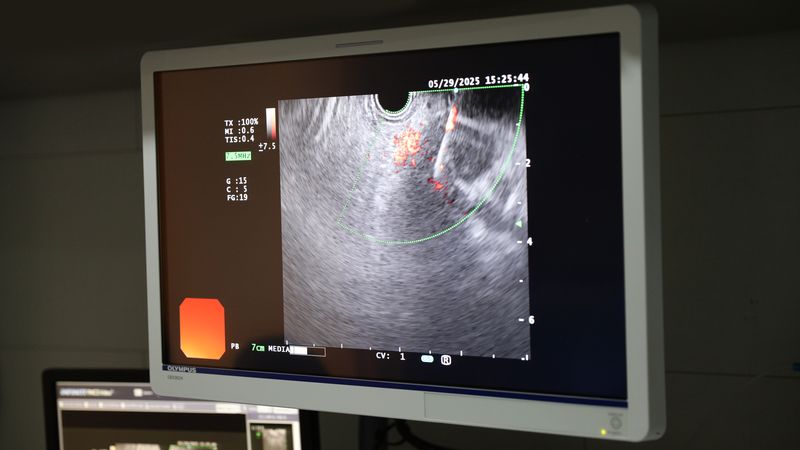

췌장·담도계 질환 ‘내시경 초음파(EUS) 유도하 세침흡입술(EUS-FNA/B) 및 조직검사’ 첫 성공적 시행

삼육부산병원 소화기내과 김진남 과장은 최근 내시경 초음파(EUS) 유도하 세침흡인검사를 통해 췌장 및 간 병변에 대한 조직검사를 성공적으로 시행했다.

이에 따라 정확한 진단을 위해 내시경 초음파를 통한 조직검사를 시행했다.

내시경 초음파(endoscopic ultrasound, EUS) 검사는 내시경 끝에 장착된 고주파의 초음파 진동자를 이용해 소화관과 주변 장기의 병변을 정밀하게 진단할 수 있다.

특히 기존 복부 초음파로는 관찰이 어려웠던 췌장과 담도 부위를 고해상도 영상으로 실시간 확인할 수 있어 보다 세밀한 진단이 가능하다.